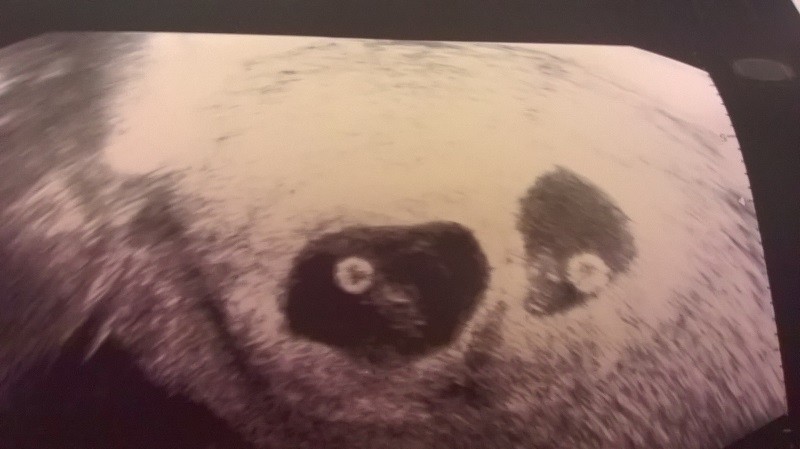

Hej dziewczynki pomyliłam wątek i wklejam tu ... Bejbiki zdrowe..jeden 14 mm albo 1.4 cm ..drugi 1.08 cm, albo 18mm ,,,słabo widać na sprzęcie doktora, mówił, że niewiele się od siebie różnią wzrostem. ciąża młodsza o niecały tydzień :)